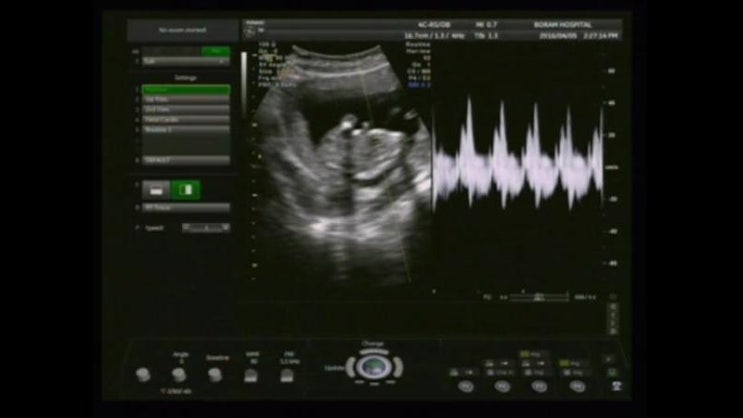

+ 12w 4d / 반전 해랑이~

+ 12w 4d / 반전 해랑이~ #. 2016.04.05 (화) &nb...